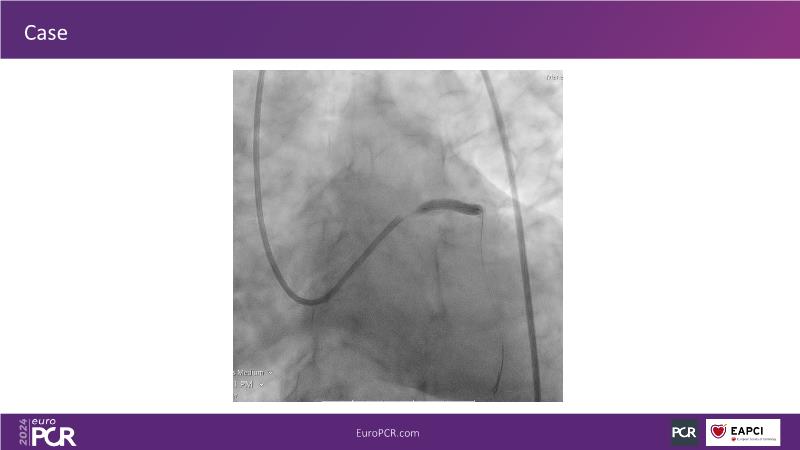

Tune into this 2024 session for insights into the latest ESC guidelines, strategies to prevent and treat no reflow, and an examination of trials like TASTE, TAPAS, and TOTAL on coronary thrombus management. Explore also the outcomes of the CHEETAH study, pondering a potential paradigm shift, and delve into a case study on thrombus removal in a patient with high thrombus burden.